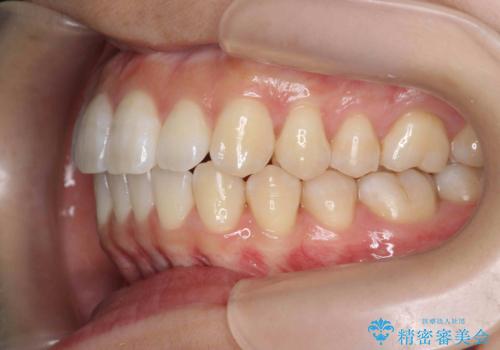

- 前歯の噛み合わせの開きの改善を求めて来院されました。

奥歯はほとんど動かさず(奥歯の噛み合わせはほとんど変えず)前歯のIPR矯正でガタつき前突感(出っ歯感)の改善を計画します。

ほとんど前歯のみの矯正治療であることからトータル14枚のマウスピースで並べるインビザラインライトによる治療を行います。